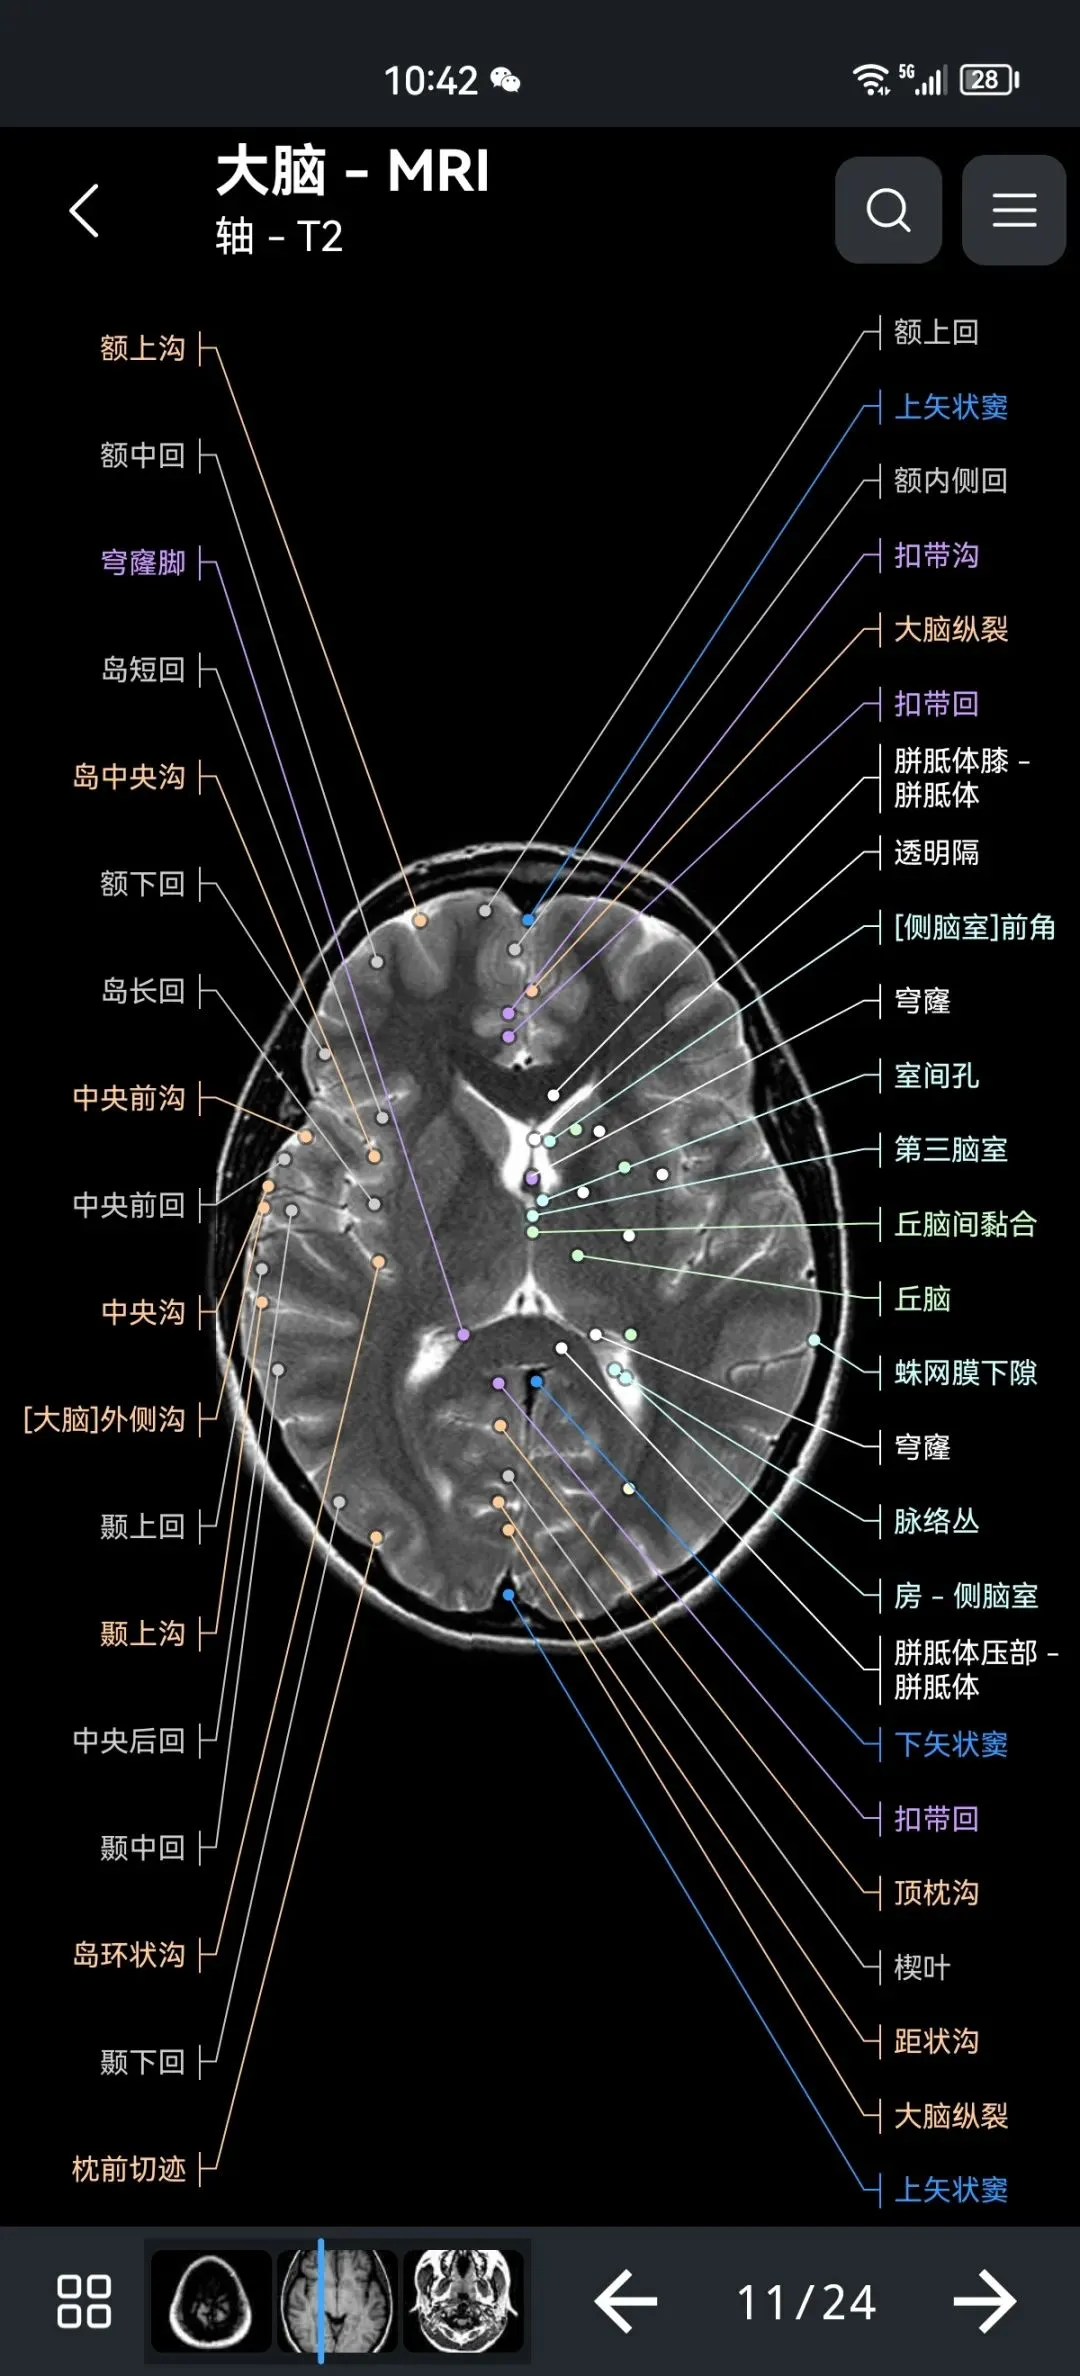

覆盖了X光、CT、MRI、断层大体解剖、核医学、介入造影、医学插图等多个模块,覆盖全身各个系统的影像解剖(正常解剖结构,无病例),其中的解剖结构高达87万个,结构标注超精细,超高清图像,历时两年研发设计完成✅。